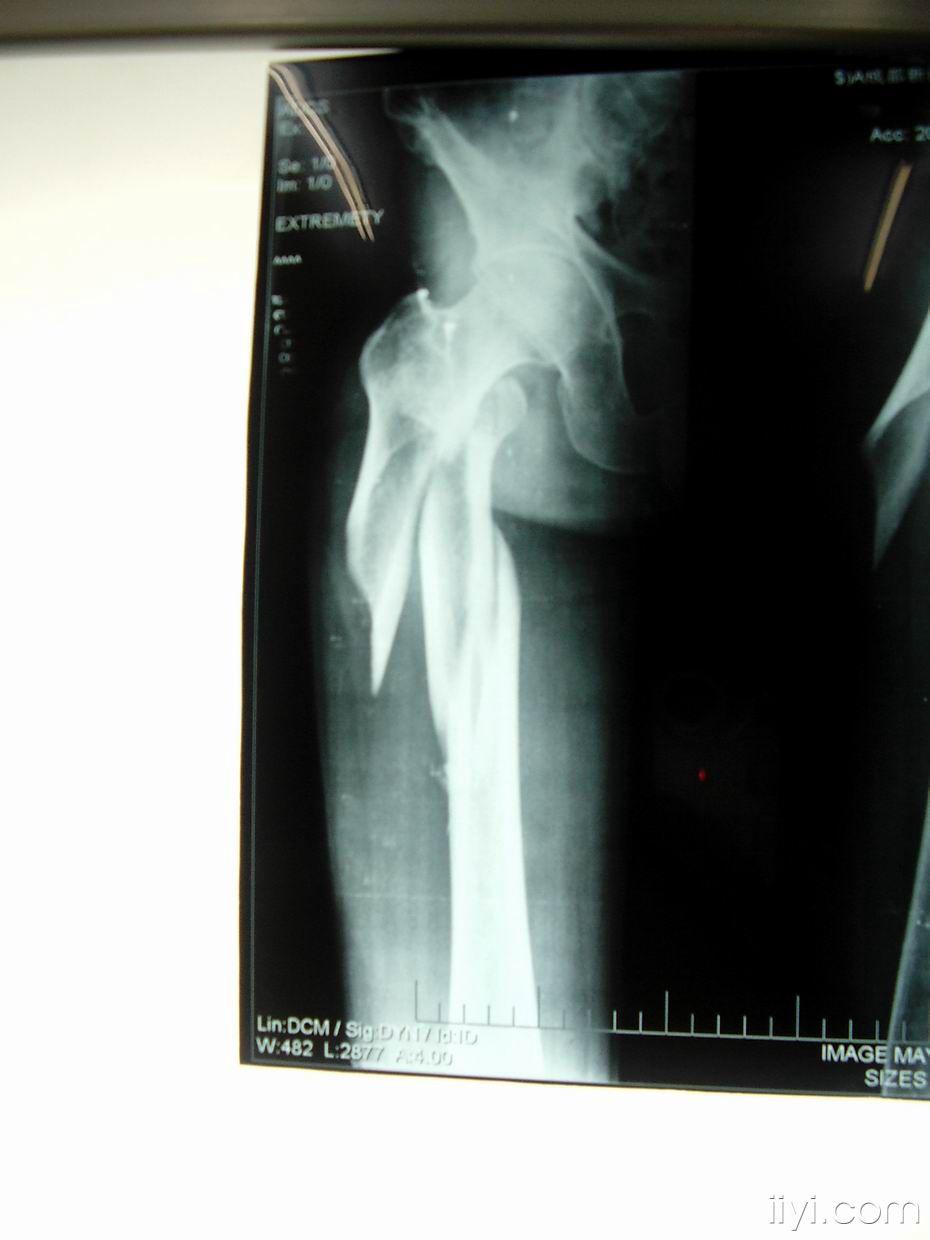

患者张某某,男,64岁,右股骨转子间骨折

图片尺寸1572x1199